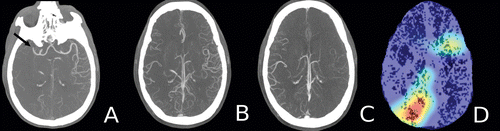

Axial maximum intensity projection images and a heat map in a 60-year old man who presented to the emergency department with new onset left-sided weakness. A, Arterial (phase 1) image shows an abrupt occlusion of the distal M1 branch of the right middle cerebral artery (arrow) with paucity of distal vasculature. B, Venous (phase 2) image shows subtle asymmetry with minimal increased vascularity in the contralateral left hemisphere. C, Late venous (phase 3) image shows prominent increased opacification of the ipsilateral right hemispheric vasculature downstream from the occlusion. D, Heat map shows the most discriminative region (red) that the model used for the correct prediction. Courtesy: Radiology